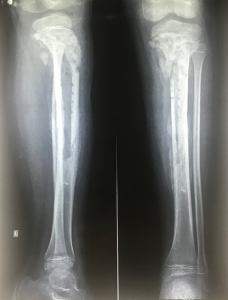

La radiografía simple debe ser siempre el primer estudio para descartar fracturas o tumores, aunque es importante recordar que suele ser normal durante los primeros 7 a 14 días de la infección. Los cambios líticos y la reacción perióstica son hallazgos tardíos. Por el contrario, la Resonancia Magnética (RM) con contraste es el estándar de oro, con una sensibilidad superior al 95% para detectar edema de médula ósea en las primeras 24 a 48 horas. La ecografía es útil principalmente para identificar derrames articulares asociados o colecciones subperiósticas.